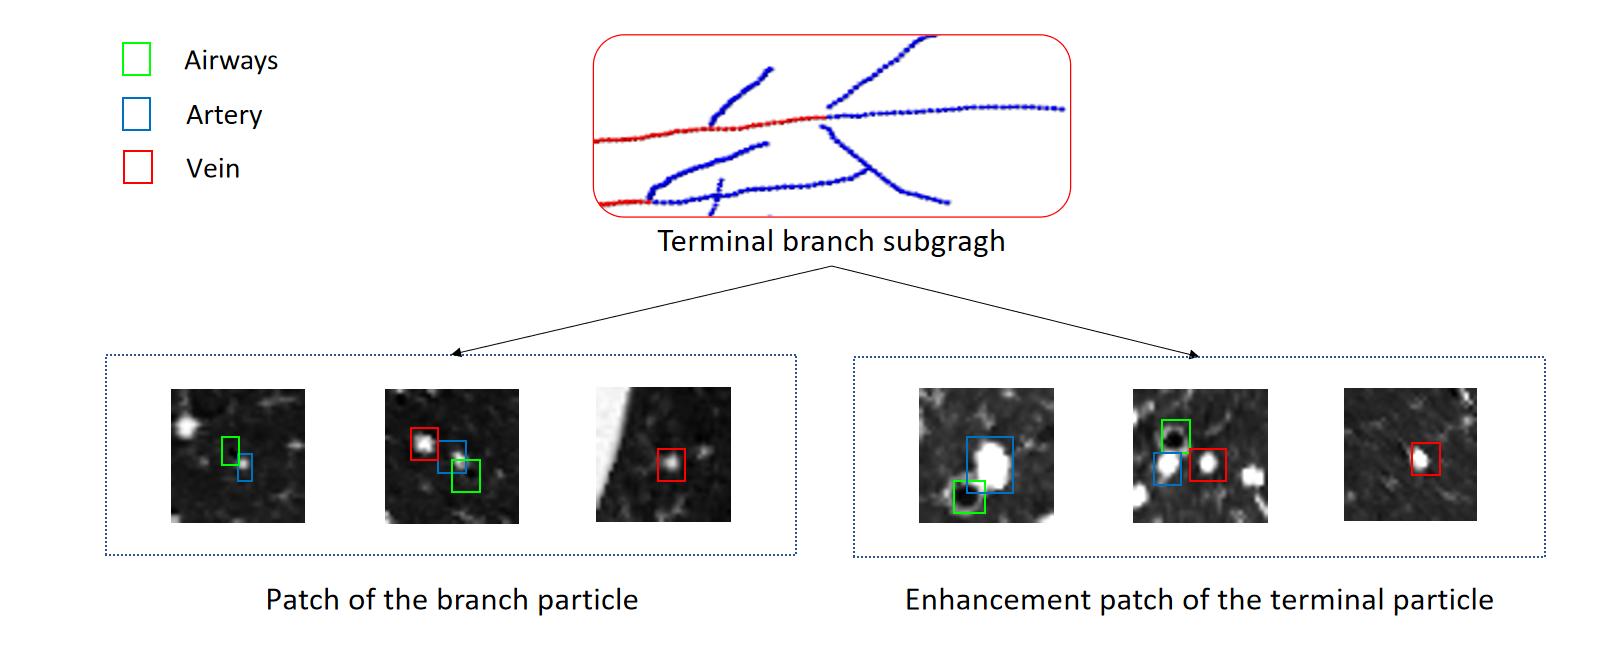

We propose that the Twin-Pipe network is expected to learn the difference of A/V characteristics caused by different levels and improve the accuracy of the preliminary classification. In this paper, a Twin-Pipe network is designed, in which one pipe network trains the full vessel graph to learn the image information and global connectivity, and the other pipe network specially trains the terminal vessel graph to learn the terminal structure characteristics. Finally, the preliminary classification results are obtained through the mutual correction module. The terminal vessel graph is the set of terminal branches in the full vessel graph, and the extraction process is shown in Fig. 9.

Aiming at the physiological feature of obvious accompanying artery at the end of trachea, for this purpose, the CT original image and vascular enhancement image serve as the input patch of another pipe of Twin-Pipe network, expecting to learn some additional distinguishing features of pulmonary arteries and veins. We perform vascular enhancement and normalization on the original image to enhance the differences between vessels and bronchi. Twin-Pipe network structure design in this paper is shown in the Fig. 10. Fig. 11 shows a case of extraction of terminal vessel particle and patch.